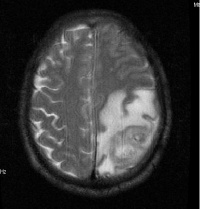

4.脑脓肿:脑脓肿患儿多有中耳炎或头部外伤史,有时继发于脓毒败血症。常伴先天性心脏病。脑脓肿患儿除脑膜炎及颅压高症状外,往往有局灶性脑征。脑脊液改变在未继发化脓性脑膜炎时,细胞数可从正常到数百,多数为淋巴细胞,糖及氯化物多正常,蛋白正常或增高。鉴别诊断借助于超声波、脑电图、脑CT及脑血管造影等检查。

5.但脑瘤与结脑不同处为: ①较少发热。②抽搐较少见,即使有抽搐也多是抽后神志清楚,与晚期结脑患儿在抽搐后即陷入昏迷不同。③昏迷较少见。④颅压高症状与脑征不相平行。⑤脑脊液改变甚少或轻微。⑥结素试验阴性,肺部正常。为确诊脑瘤应及时作脑CT扫描以协助诊断。